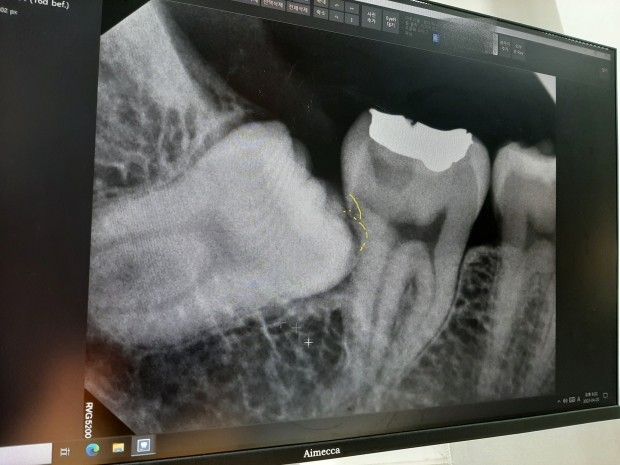

발치 전 사랑니 사진입니다.

1. 어금니 중간쯤에 푹 파인 부위가 충치가 있는 부위라고 설명해주시던데 현대의학으로는 치료는 어려우며 경과를 지켜보는 수 밖에 없다고 하셨는데 그럼 몇개월마다 사진을 찍어봐야 할까요?

1. 충치가 잇몸 하방 뼈 있는 곳과 아주 근접해 있기 때문에 치료가 쉽지 않다는 의미입니다. 충치 경과는 6개월에 한번 정도 내원하셔서 체크하시면 됩니다. (충치일 수도 있고 치근이라고 하는 치아 뿌리가 사랑니에 의해 흡수된 것일 수도 있습니다.)